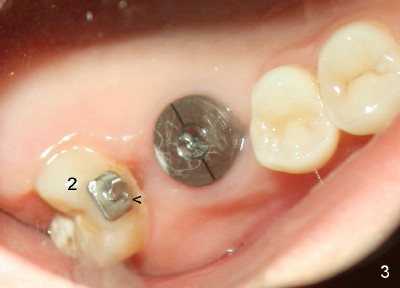

Fig.3 shows the implant 3 months post placement. It is not placed too superficial. The tooth #2 appears to be more distalized (using a lingual button as mesial fixed point (Fig.3 <)) than that in Fig.2.

A 6 mm 0 degree unipost (5 mm in length) is used. There is more trimming with larger uniposts (larger trimming surface). On the other hand, too aggressive trimming is avoided to prevent poor retention. In this case, the unipost is trimmed so much that the Tatum screw driver does not fit. A cross pattern has to be made on the coronal end of the unipost in order to use a household screw driver to engage the unipost into the implant well.